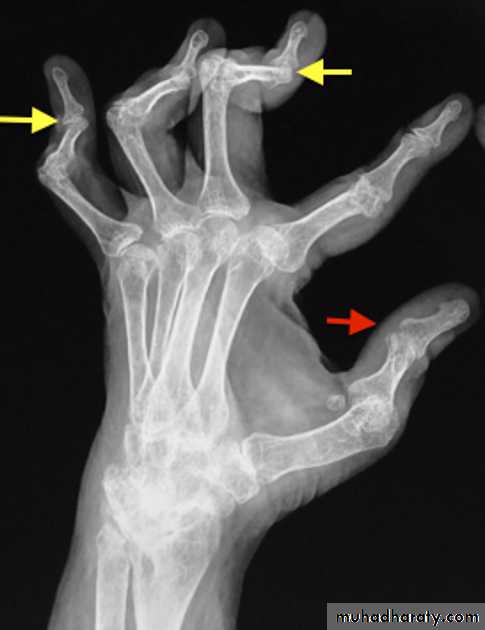

Swan neck deformity is a deformity of the digits that consists of:

hyperextension of the PIP jointscompensatory flexion of the DIP joints

Swan neck deformity is seen in :

1.rheumatoid arthritis (classical association)

2.post-traumatic:Mallet finger

3.scleroderma

4.psoriatic arthritis